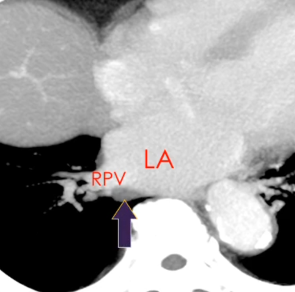

Sinus Oblique

Sinus Veineux Pulmonaire